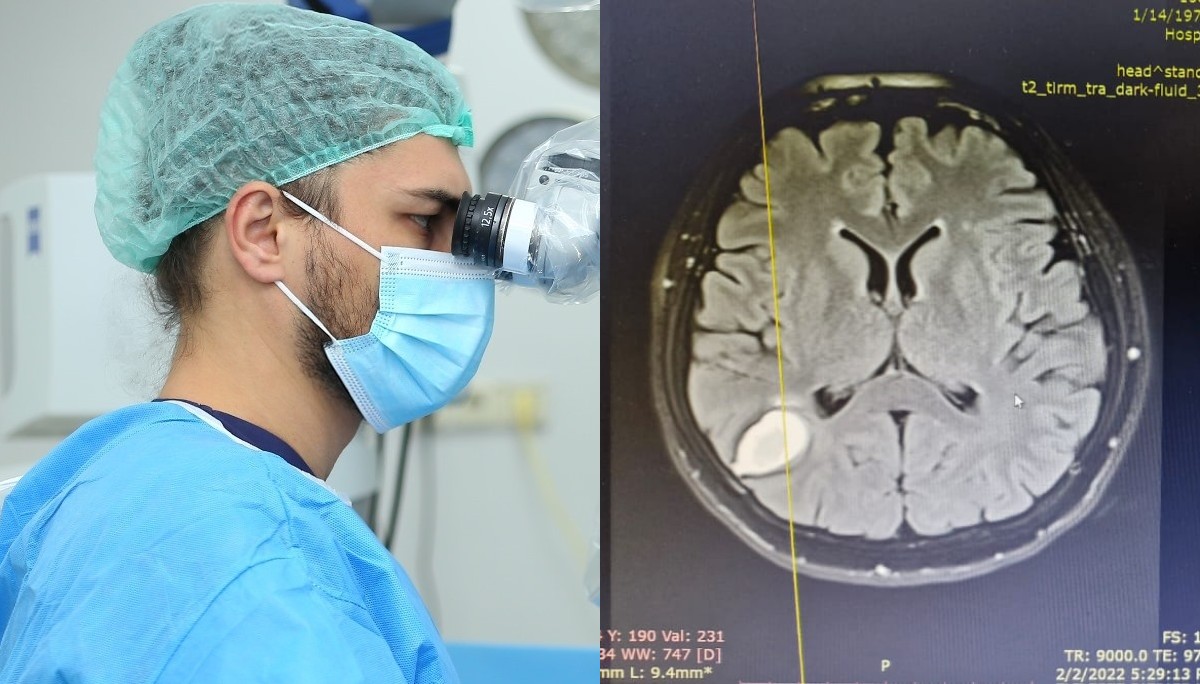

Объемную опухоль в правой теменной доле врачи «соседнего государства» выявили у женщины около трех лет назад во время МРТ после секторальной резекции молочной железы из-за онкозаболевания.

Секания предложил ей провести удаление новообразования и начал повторные исследования. По результатам МРТ выяснилось, что местоположение опухоли изменилась – вместо теменной доли теперь она была в височной. Специалисты предположили, что подобные изменения связаны с образованием новых метостазов. «Однако во время операции в головном мозге был найден живой солитер размером до 15 см, который перемещался внутри мозга», — рассказывает нейрохирург.